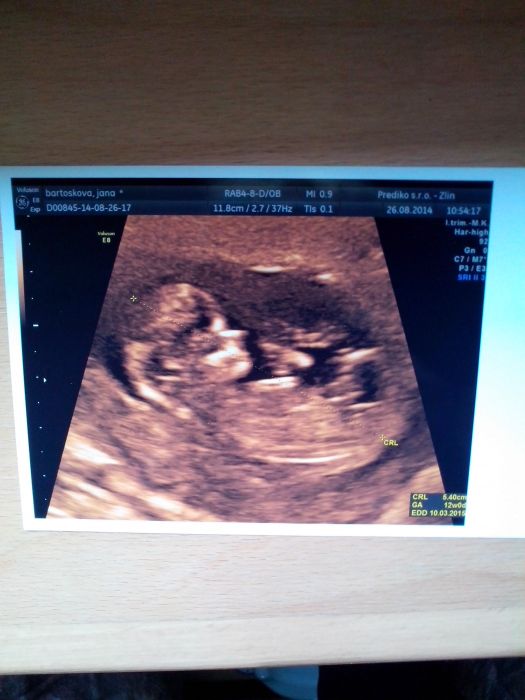

Kacabo, sousedce řekli 3 měsíce. Od 2 to zkouší. Máš to za sebou, už bude jen líp.Já byla dneska na genetice. Mám sice jen ultrazvuk. Dopadl dobře, nos máme obrovský , šíjovè pro jasnění 1, 45. Tak krásný neměl ani jeden kluk. Honza 2,2 .Tam byl strach... Tak snad ta krev bude taky OK... Akorát mám Place nTu pořád dole , snad prý ještě vyleze...